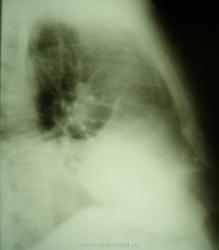

Женщина обратилась с жалобами по поводу кашля и температуры, которая поднимается до38 град. Был сделан снимок в двух проекциях.

Хочется спросить уважаемых коллег: "Есть ли там плевральный выпот"?

Массивное затемнение "вне анатомических границ", чаще всего дает выпот.

И слева, кажется, тоже.Выпот, даже не сомневайтесь.Причем "добрый"( в смысле, жидкости много).

Правосторонний средний гидроторакс. Позвонки одинаковой высоты.

Коллеги! А на ателектаз нижней и средней долей совсем не похоже?

Такой ателектаз средостение хорошенько бы потянул.

Потянул-бы, если-бы выпота справа не было. А так плюс - на минус - средостение-то на месте, при значительном выпоте справа.

Стоит подумать над версией предложенной коллегой lupan